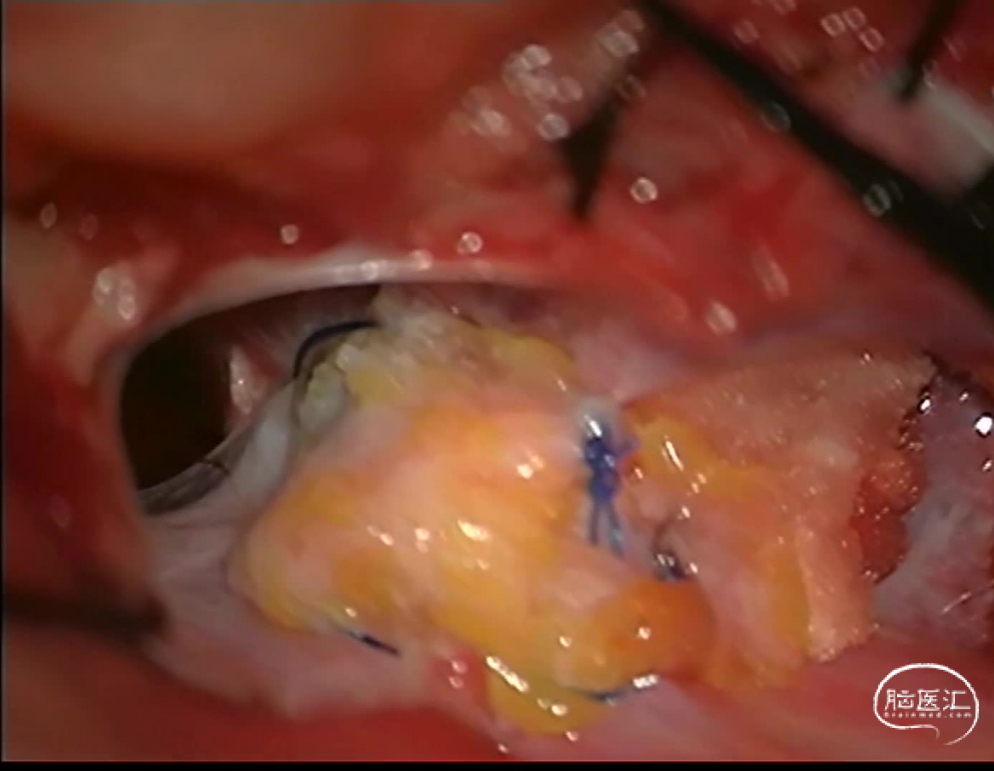

图2 手术过程: 病灶位于硬脊膜夹层见,见清亮脑脊液,有多个分隔,内镜下探查并开通数个分隔,漏口位于L1水平,以自体组织进行修补交通口。